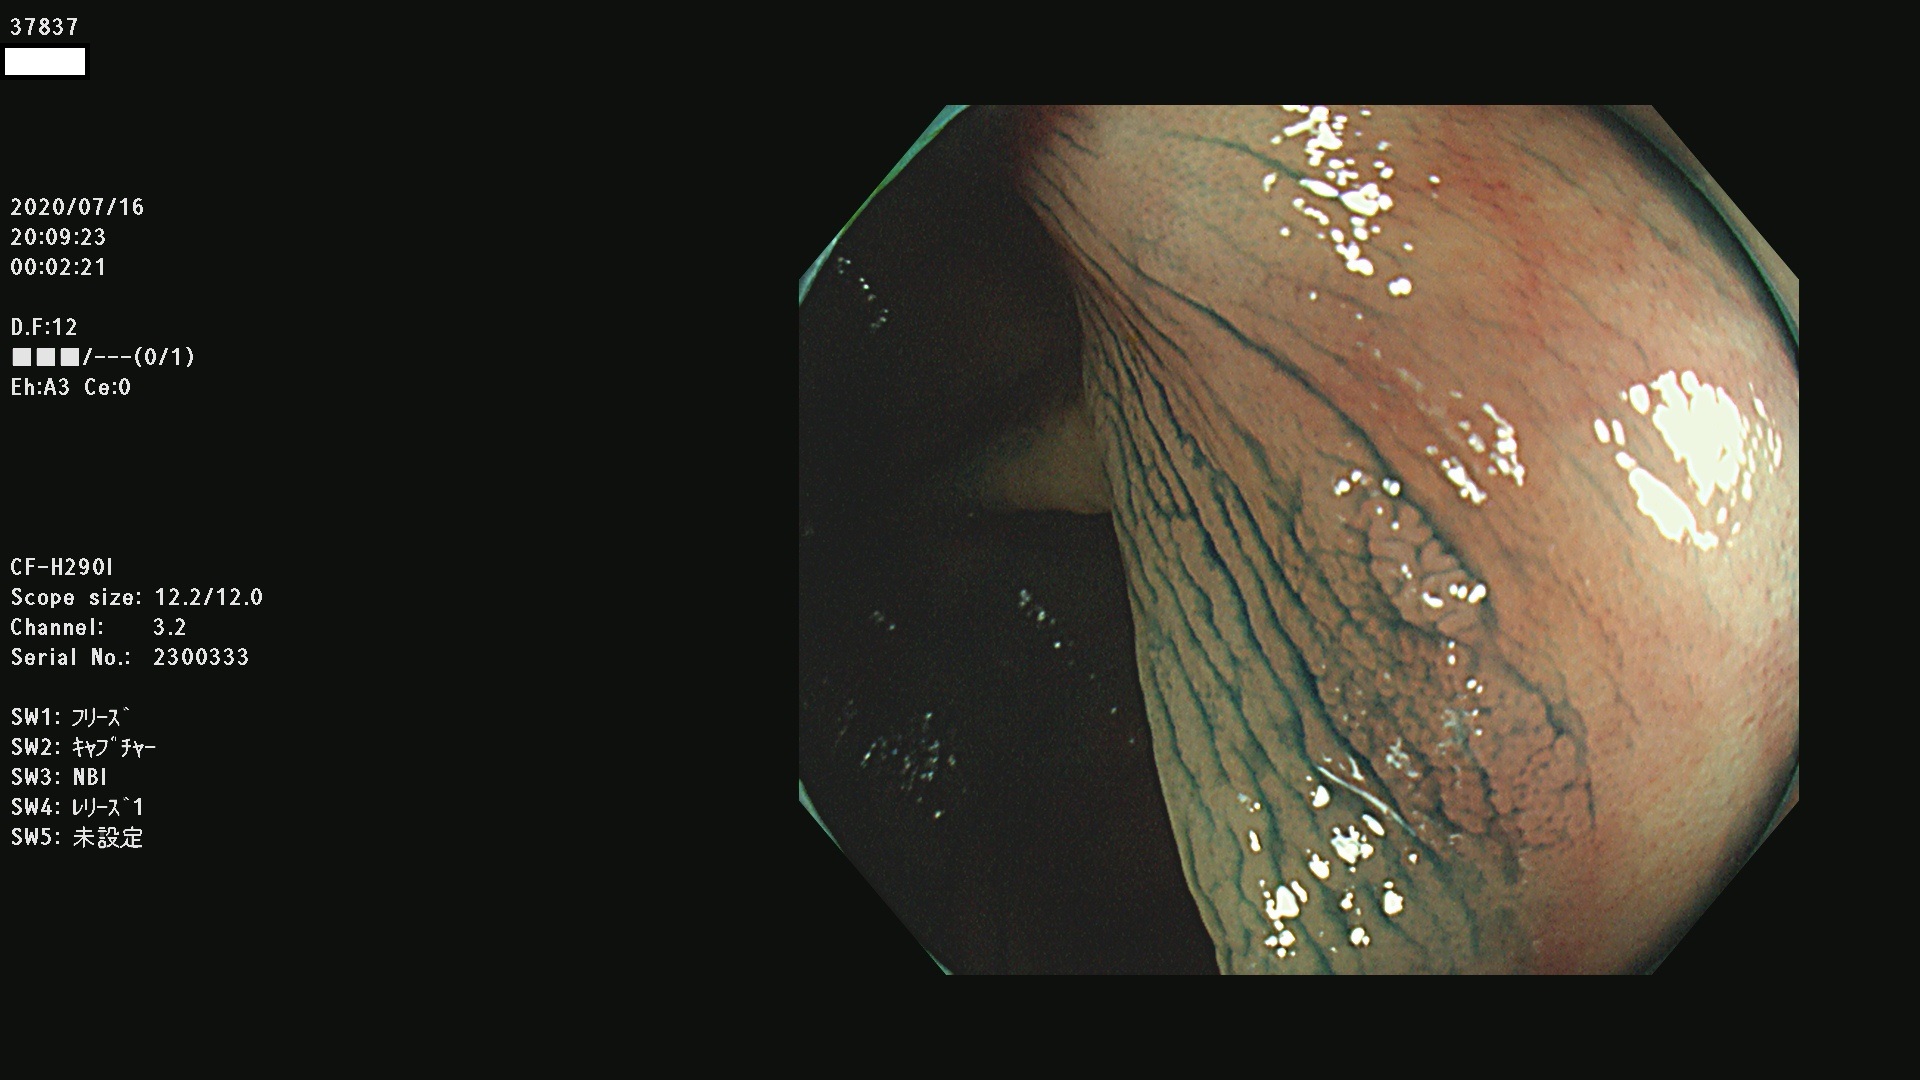

腺腫発見率 75 % (カルテ番号 37800〜37899の100名の方の検査結果で集計)大腸癌検診最新情報

以下のカルテ番号の方に腺腫(Adenoma,Group3〜5)が見つかりました(集計法)

37800(SSAPのみ) 37801 37802 37803 37804 37805 37806 37807 37808 37809(SSAPのみ) 37810 37811 37812 37813 37814 37815 37817 37818 37819 37820 37821 37822 37824 37825 37826 37827 37828 37829 37832 37833 37836 37837(SSAPのみ) 37839 37840 37842 37844 37845(SSAPのみ) 37847 37849 37850 37851 37852 37853(SSAPのみ) 37855 37856 37857 37860 37861 37862 37863 37864 37867 37868 37871 37874 37876 37877 37879 37880 37881 37882 37883 37886 37887 37888 37889 37890 37891 37892 37893 37894 37896 37897 37898 37899

発見困難で危険性の高い平坦型病変(上記100名より抽出) ![]()